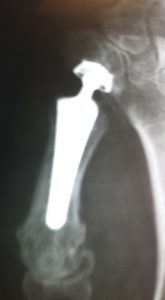

Figure 4 Prothèse trapézo métacarpienne

La prothèse trapézo métacarpienne consiste en remplacement du cartilage usé par une prothèse qui est basé sur le même principe que la prothèse de hanche miniature.